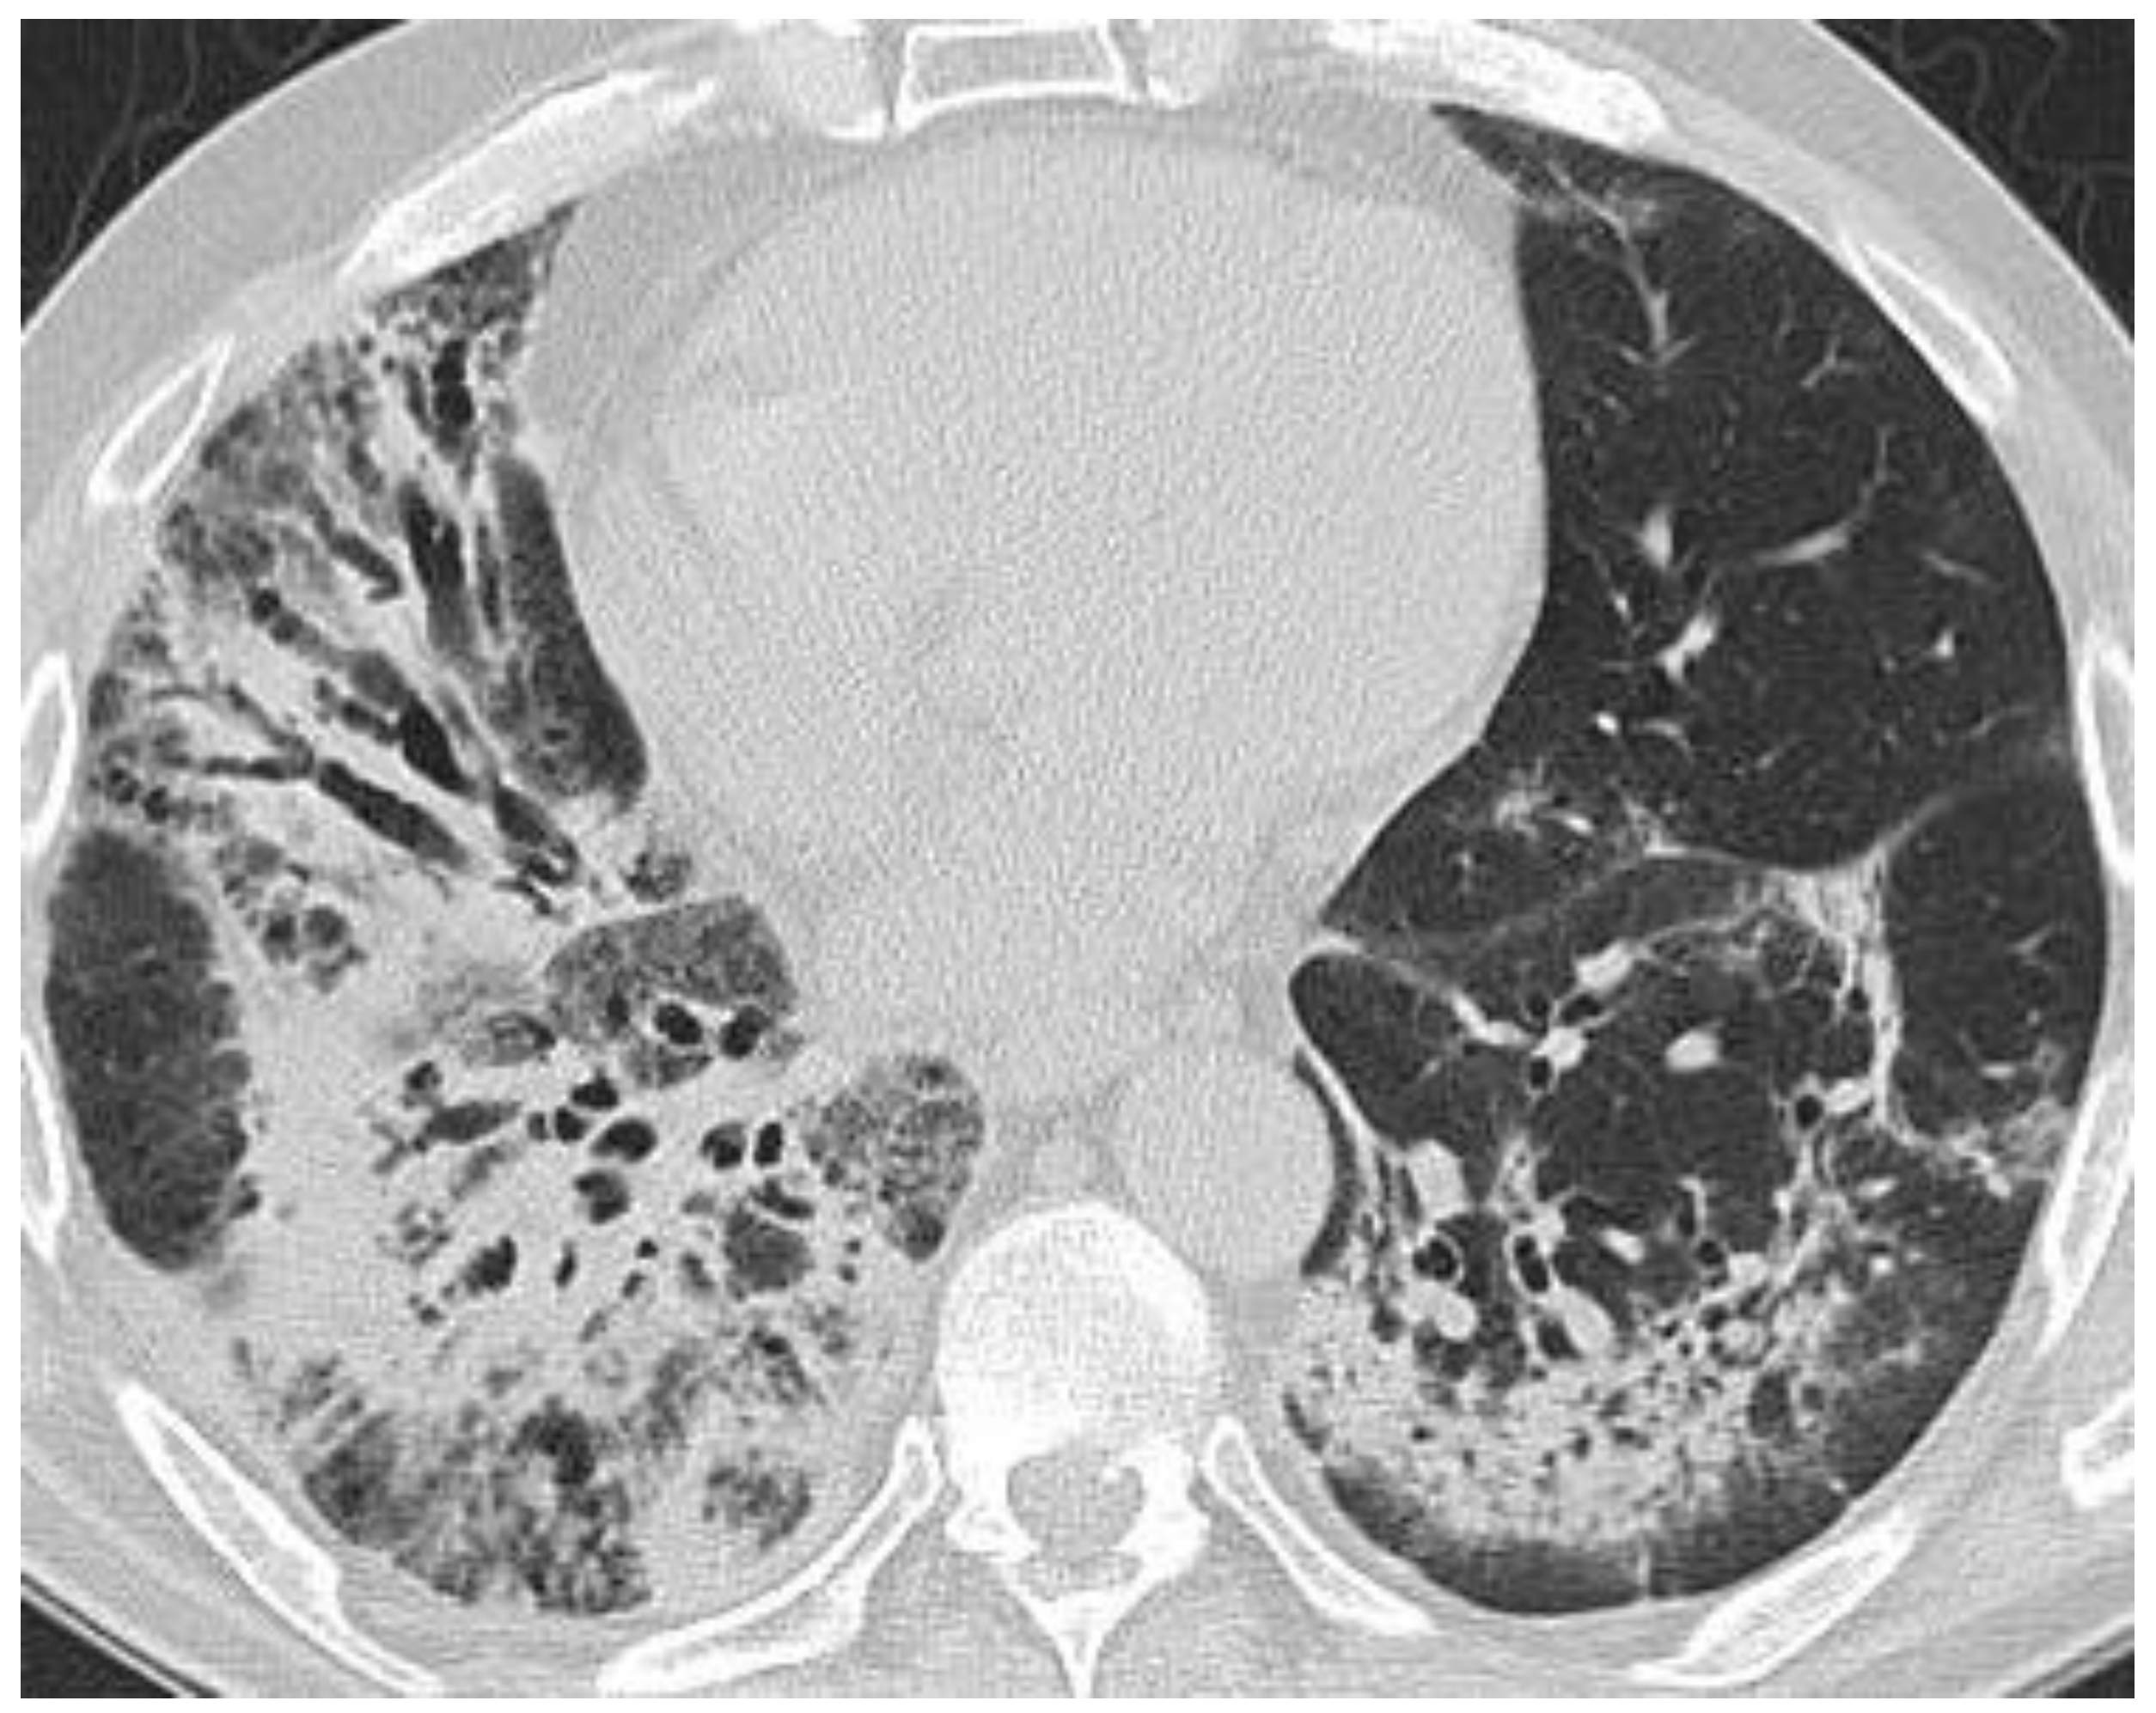

5. ICI Therapy-Related Pneumonitis